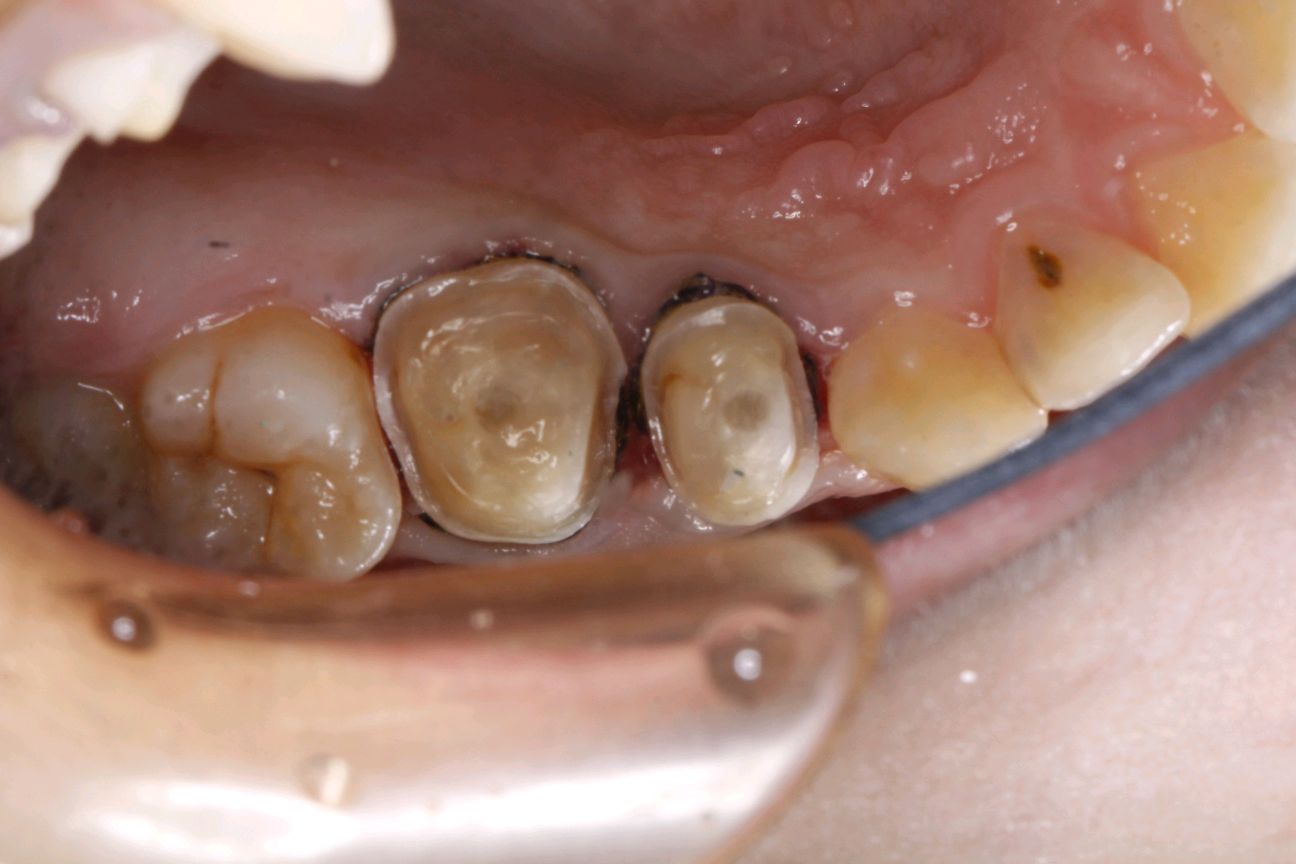

传统的补牙方法就是把蛀的部分磨掉,然后再补上材料,最后进行抛光。

传统补牙方法方便快捷,能一次完成,但是由于传统的补牙是在口内一次性完成的,整个的操作过程受到口腔唾液,以及医生在口腔内操作空间太小等等一些客观的,并且很难避免的因素的影响,最终使得补上去牙齿寿命不长,很可能引发脱落和继发龋。而且像那种面积较大的龋坏和特殊部位的龋坏,用传统补牙方法也不适用。

嵌体是在口外石膏模型上由专门的牙科技师制作出来的,然后再由临床医生将其戴入患者口内,最终粘固形成。

嵌体的整个的制作过程完全避免了在口腔内部操作的干扰因素,这就使得嵌体的制作比传统的补牙要更精细;

边缘密合性好、咀嚼备感舒适,避免了传统补牙容易脱落、嵌塞食物并造成继发龋等问题;